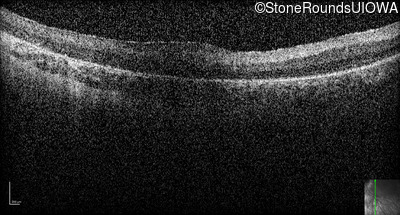

Optical Coherence Tomography - Right -

Light Perception

Exemplar / OCT Stack